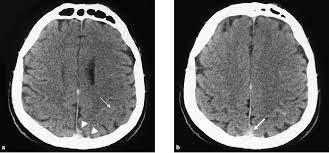

Cerebral venous sinus density on noncontrast ct correlates with hematocrit. Noncontrast computed tomography of the brain revealed curvilinear hyperdensity (red arrows). Aha scientific statements ⅲ venous thrombosis ⅲ sinus thrombosis, intracranial ⅲ brain infarction figure 1. See that article for a discussion of that specific clinical entity. Cerebral venous sinus thrombosis in children:

Common subtypes include transverse sinus thrombosis and superior sagittal sinus. What causes cerebral venous sinus thrombosis? Cerebral venous sinus thrombosis occurs when a blood clot forms in the brain's venous sinuses. Cerebral venous thrombosis (cvt) is an uncommon disorder in the general population. (iii) clinical and radiological features of brain lesions in csvt compared with arterial stroke, and (iv) a low threshold for ct or mr venography in children with acute neurological symptoms is essential.

Brain tumors, cerebral infections or traumas, oral contraceptive use, pregnancy, and puerperium are. Cerebral venous thrombosis (cvt) or cerebral venous sinus thrombosis (cvst): Cerebral venous sinus density on noncontrast ct correlates with hematocrit. Cerebral venous thrombosis (cvt) is an uncommon disorder in the general population. Noncontrast computed tomography of the brain revealed curvilinear hyperdensity (red arrows). Cerebral venous and sinus thrombosis (cvst) is a rare disease responsible for less than 1% from the total of avc causes (bajenaru, 2010). The venous circulation of the brain is done. A statement for healthcare professionals from the american heart association/american stroke association.